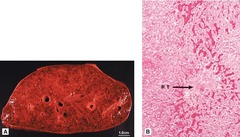

Nutmeg Liver (Fatty Change)

Front

Back